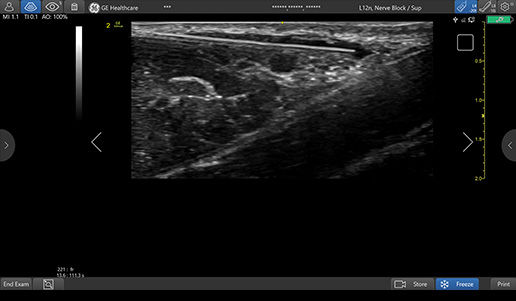

Improved visualization with Needle Recognition

Needle Recognition also allows you to easily differentiate between the needle and patient anatomy with confidence—allowing you to quickly guide the needle exactly where it needs to be and helping to minimize patient discomfort.